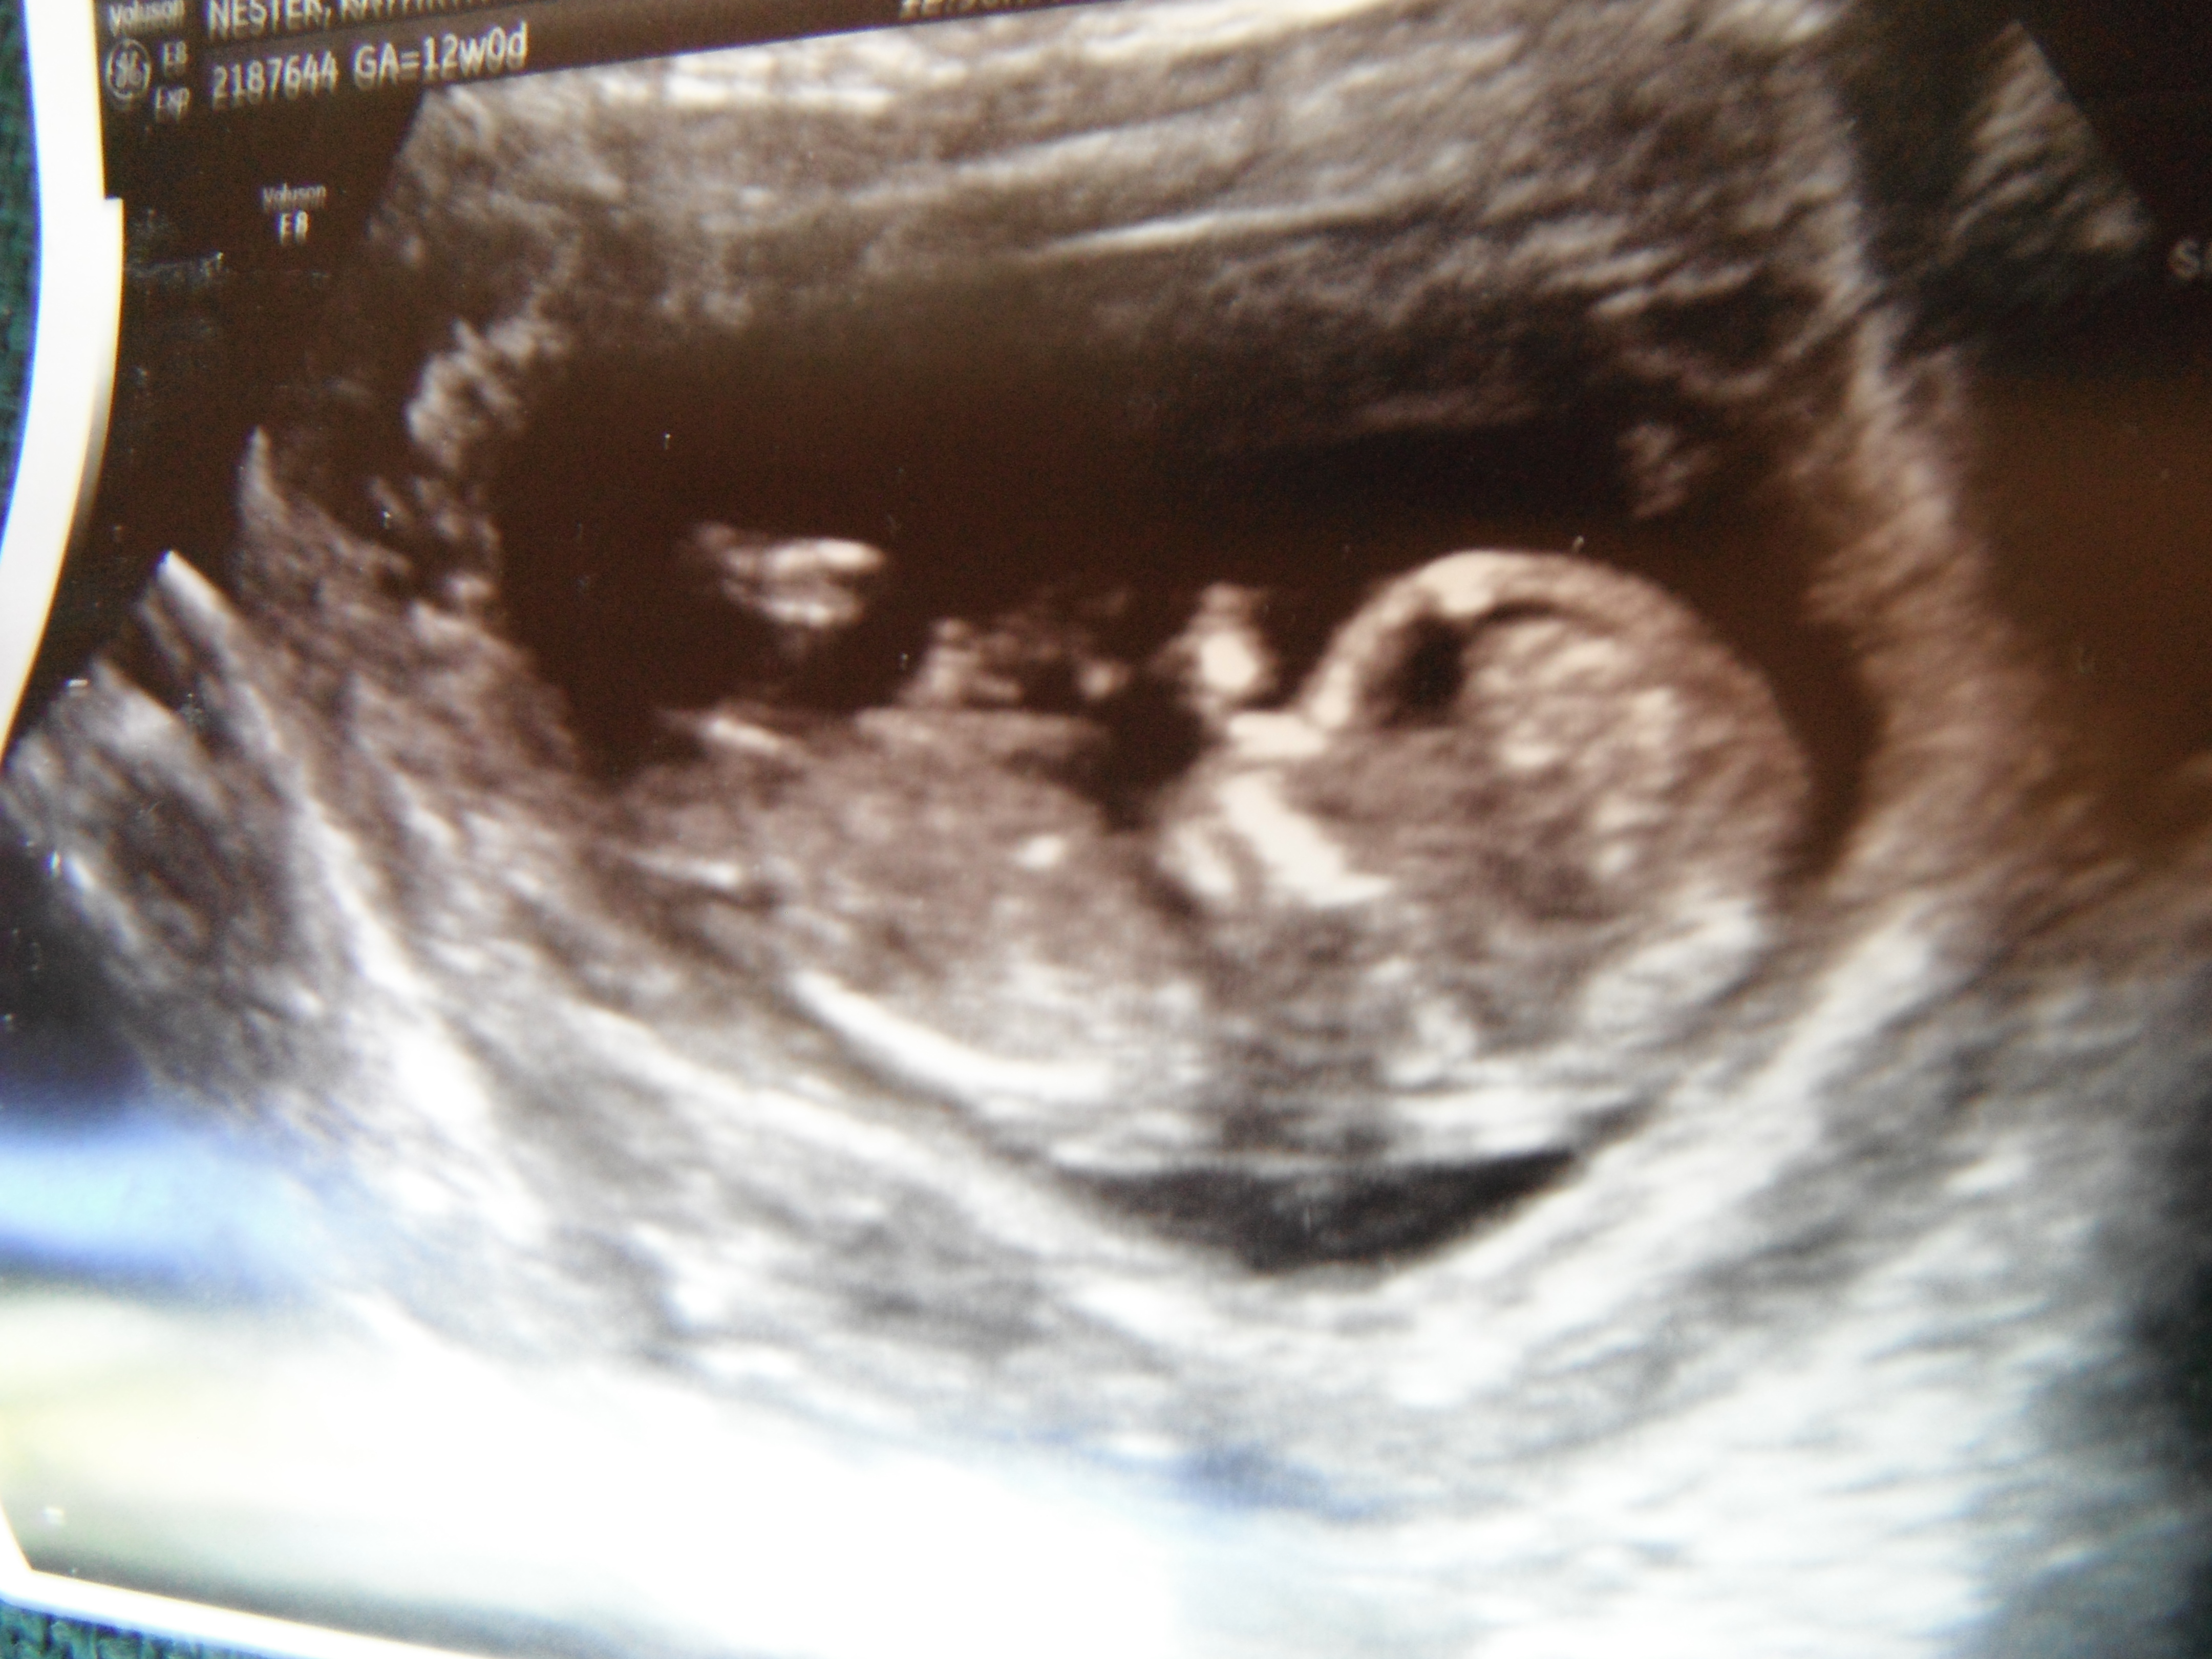

would love a NUB GUESS on our "whoops we got pregnant before we could sway" baby! :)

Atomic, I said I'd be back with gender... though at 12 weeks it's just a guess...

Tech didn't want to say anything - but after I coerced her...she said, "Initially I thought I saw boy parts, then as the scan went on, I mentally changed my guess."

Hard to tell so early...but is anyone else brave enough to give me their thoughts?

Four, I"m not sure if there's anything to go on in this shot? It's like the critical bits are not visible. Did you get any more pics??

i have this one other body shot - didn't think it was as great a pic - but maybe a better nub shot?

i can't believe i thought the initial pic i posted (which i can tell now is baby's foot/leg) was his/her nubber! haha.... oy. i am certainly no expert!

I would say the second one is a good GIRL nub!

based on 2nd pic, i'd lean GIRL. GL

Girl

Also thinking girl :-)

I think girl too, fx for you